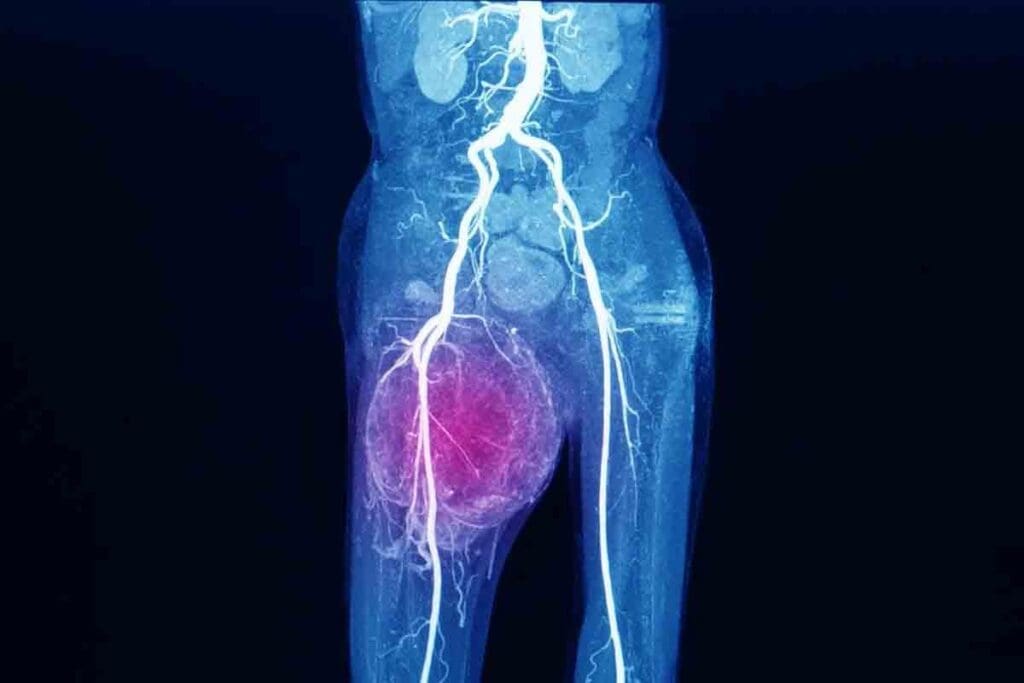

Hip Sarcoma and Other Pelvic Presentations

The pelvis is a big spot for Ewing sarcoma, with hip sarcoma being a common type. Pelvic Ewing sarcoma is hard to spot because it’s deep and symptoms are not clear. It usually causes pain and swelling in the hip or pelvic area.

Imaging is a big part of diagnosing Ewing Sarcoma. Tools like X-rays, MRI, CT, and PET scans help see the tumor’s size and location.

- CT scans measure the tumor’s size and its position.

- PET scans find if the disease has spread.